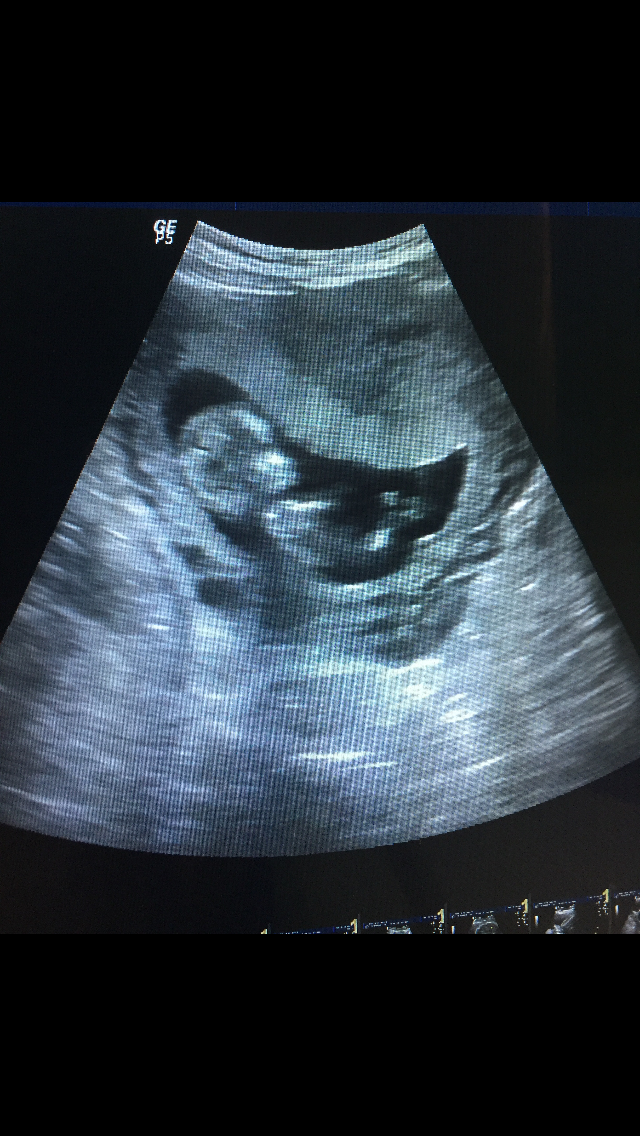

انا عضوه جديده معكم واتابعكمم من فتره وانا حامل بالشهر الرابع ولادتي بذي الحجه بالعيد الله يهون علي وعليكم يارب

بنات من عندها صورة للجنين بالشهر الثاني شوفوها وطبقو عليها نظري رامزي خصوصا للي عرفو جنس الجنين ثلاث من جماعتنا ضبطت معهم ودي انزل صورة التجربه لكن ماعرفت انزل صور من جوالي للتطبيق

انا مثل نون احب اخمن واحب اشوف صور السونار

بس اكيد احط في بالي ان احتمال الغلط وارد وبقوه

هذي باخر الاسبوع ال١٢